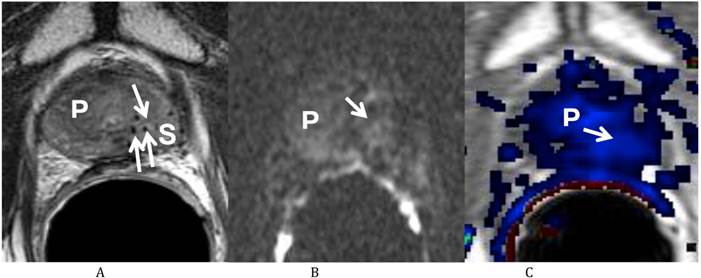

He was sent for a multi-parametric prostate MRI on July 26, 2011 (Fig 1). A body coil and endorectal coil were utilized for this study on a 1.5T magnet. Axial T2, sagittal T2 and coronal T2-weighted images, diffusion weighted images with b50, 400 and 1000, and dynamic contrast enhanced images were obtained through the prostate. A total of 20 ml of ProHance was administered intravenously. The MRI findings revealed a vague low T2-weighted focus in the left mid gland measuring about 8.6 mm x 11 mm in size. This low T2 signal focus was noted to extend to the prostate capsule without clear evidence of extracapsular extension of disease. There was correlating diffusion restriction in this region on b1000 image (Fig 1B). In addition, on the dynamic contrast-enhanced images, there was also a corresponding early enhancing focus with rapid washout (Fig 1C), correlating with the region at the left mid gland of the peripheral zone. This lesion corresponds to the region positive for recurrent disease on the most recent biopsy. In addition, there was generalized decreased T2 signal of the prostate consistent with prior radiation treatment, but there were no other focal abnormalities. Both seminal vesicles were unremarkable and there was no pelvic lymphadenopathy observed on T1-weighted images.

Figure 1

Multiparametric Prostate MRI demonstrating recurrent prostate cancer at the left mid peripheral zone. (A) Axial T2 weighted image shows a vague low T2 signal focus at the left mid gland of the peripheral zone (arrow) of the prostate (P). (B) Diffusion weighted image (b 1000) shows a high signal focus at the left mid gland of the peripheral zone (arrow) of the prostate (P) consistent with diffusion restriction. (C) Axial post dynamic contrast image shows a lesion at the left mid gland of the peripheral zone (arrow) of the prostate (P) with rapid wash in and wash out, consistent with the biopsy proven recurrent prostate cancer.

He returned on October 12, 2011 for his first post-treatment follow up examination. On presentation he described nocturia of 0-1 time per night and a daytime voiding interval of 1-2 hours. He was having moderate urinary urgency and a weak urinary stream with associated straining, but denied any incomplete bladder emptying, dysuria, hematuria or urinary incontinence. He further denied any GI complaints and stated that his erections were firm for intercourse without medication. His self-assessed American Urological Association (AUA) prostate symptom score was 21 (pre-salvage AUA symptom score 5) and his Sexual Health Inventory for Men (SHIM) score was 22. He was sent for repeat multi-parametric prostate MRI on October 25, 2011 (Fig. 2). The images showed that the previously visualized lesion in the left mid gland of the peripheral zone with rapid contrast wash in and wash out, and diffusion restriction, was no longer visualized. This was consistent with a response to treatment.

Figure 2

Multiparametric Prostate MRI following focal salvage brachytherapy demonstrating resolution of the recurrent prostate cancer at the left mid peripheral zone. (A) Axial T2 weighted image shows the previously visualized vague low T2 signal focus at the left mid gland of the peripheral zone of the prostate (P) is less well seen (arrow). Multiple radiation seeds at the region (S) are noted. (B) Diffusion weighted image (b 1000) shows resolution (arrow) of the previously visualized high signal focus at the left mid gland of the peripheral zone of the prostate (P). (C) Axial post dynamic contrast image shows resolution (arrow) of the lesion at the left mid gland of the peripheral zone of the prostate (P).